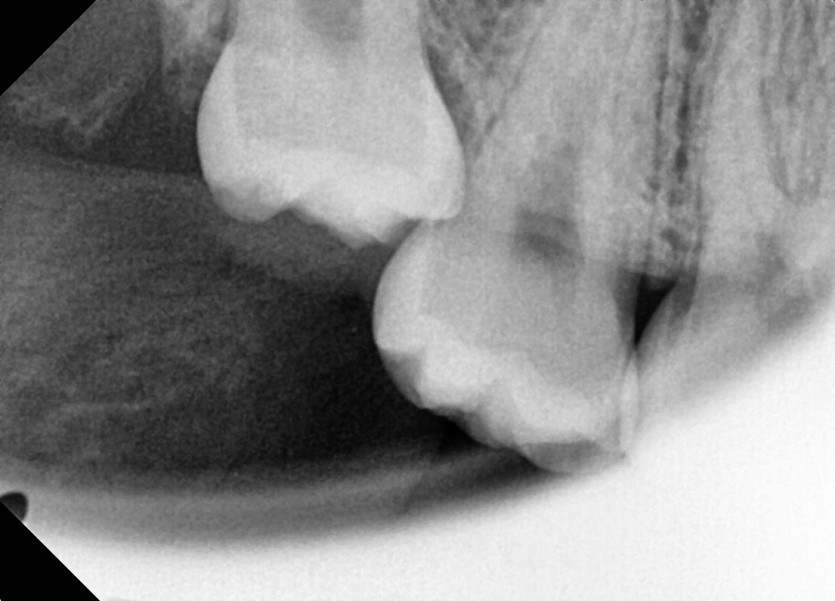

#18,28,38,48 사랑니 발치

구강 외과 전문의가 당일 발치했습니다.